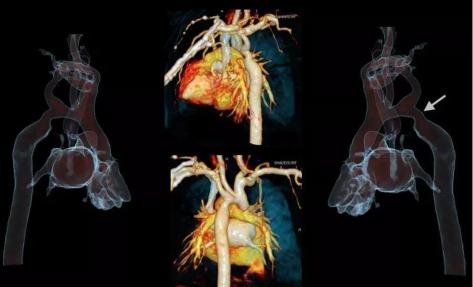

ForceCT转速可达0.25秒/圈,双套球管及探测器交叉90度设计,相当于单源CT 0.125 秒/圈,心脏成像时间分辨率66ms,真正跨越自由心跳门槛100ms,因此可以做到自由心率的心脏冠脉CTA等检查。

西门子独创的Turbo Flash模式,扫描速度达每秒73.7厘米,可在1秒内完成胸腹大血管、头颈心一站式筛查,对胸痛三联征、心脑联合成像、头胸心腹部及全程主动脉等多部位一站式联合扫描等检查都能很好的完成。

5.1 秒一站式多血管同时扫描。

1秒扫描全身+自由呼吸无禁忌成像5D功能成像